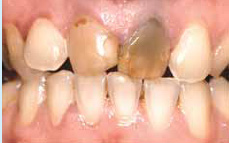

I andre tilfælde kan en krone være den eneste måde, du kan få et pænt og holdbart resultat på, fx når tanden er misfarvet eller misdannet.

Før: De midterste fortænder skal behandles med to kroner.

Efter: Tænderne med metal-keramikkroner.